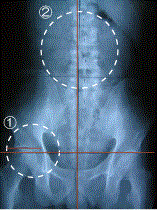

腰の改善例

治療前

治療後

①では骨盤の高さ、②では左右の歪みが改善されています。

骨盤の歪みなども必要に応じて治療を行っています。